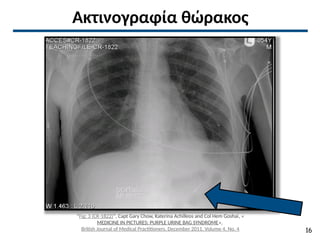

Ακτινογραφία θώρακος

“Fig: 3 (CR-1822)”, Capt Gary Chow, Katerina Achilleos and Col Hem Goshai, «

MEDICINE IN PICTURES: PURPLE URINE BAG SYNDROME»,

British Journal of Medical Practitioners, December 2011, Volume 4, No. 4 16